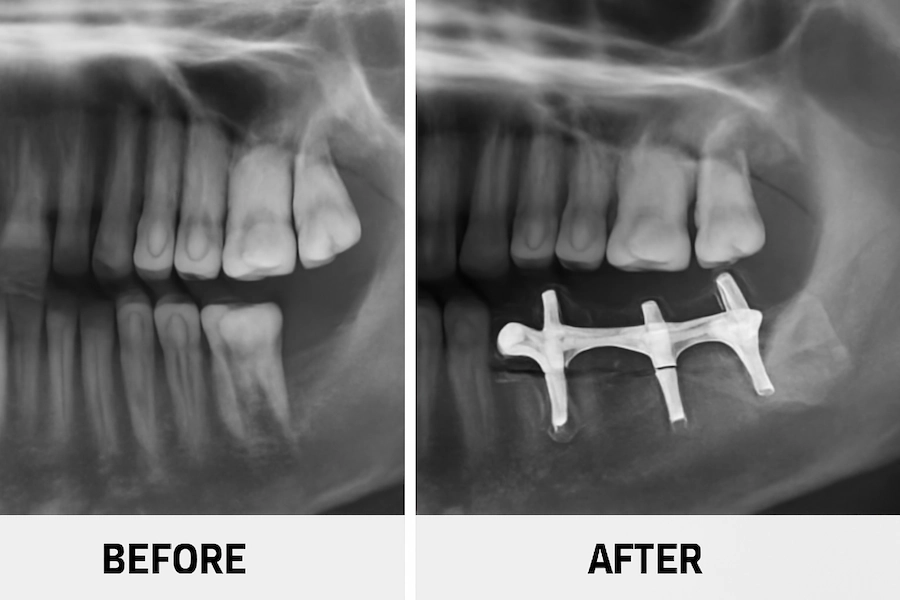

Türkiye’de Subperiostal implantlar öncesi ve sonrası

Subperiostal implant operasyonundan önce, çoğu hastanın ciddi kemik kaybı yaşadığı ve geleneksel implant prosedürlerinin oldukça zor veya imkansız olduğu durumlar mevcuttu. Ancak, hastalar operasyon sonrası fonksiyonlarını geri kazanır, tekrar güvenle gülümseyip yemek yiyebilir duruma gelirler.

İstanbul’da, Türkiye’deki LEMA Kliniği’nde, bu dönüşüm açıkça görülebilir. Kemik kaybı nedeniyle önceden imkansız görülen hastalar, Polen Akkılıç ve ekibinin desteğiyle subperiostal implantlerin muhteşem faydalarını görebilirler. LEMA Klinik öncesi ve sonrası fotoğraflar hem görünüm hem de fonksiyon açısından şaşırtıcı değişiklikleri ortaya koyuyor, hastaların gülümsemeleri ve yiyip içmeleri endişesiz hale geliyor.